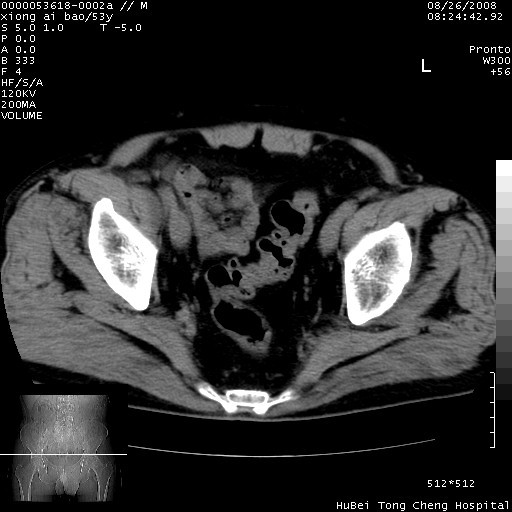

标题: CT15583:M,53Y。请老师指教分析骨盆及其他病变。 [打印本页]

标题: CT15583:M,53Y。请老师指教分析骨盆及其他病变。

股骨头坏死/腹股沟疝。

双侧股骨头无菌坏死,左侧腹股沟斜疝。

非常典型病例,双侧股骨头坏死伴双髋关节周围软组织肿胀,左腹股沟疝。

双侧股骨头坏死伴双髋关节周围软组织肿胀,左腹股沟疝。

双侧骨股头无菌性坏死,左侧腹股沟疝

双侧髋关节肿胀明显,感觉还不能排除结核。

考虑双侧髋关节结核,左侧腹股沟疝